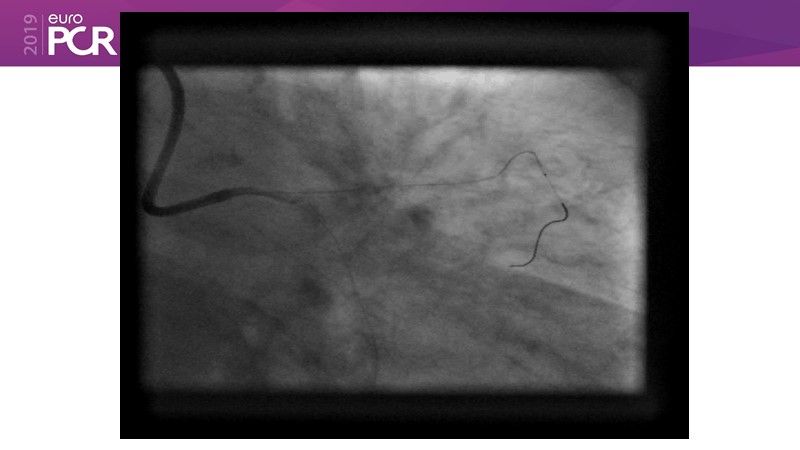

Go implant-free in de novo lesions: DCB-only strategy

Consult this session to learn about the DCB-only concept, treatment methodology and consensus group recommendations, and discover the latest scientific evidence of DCB-only in de novo lesions and in complex PCIs.